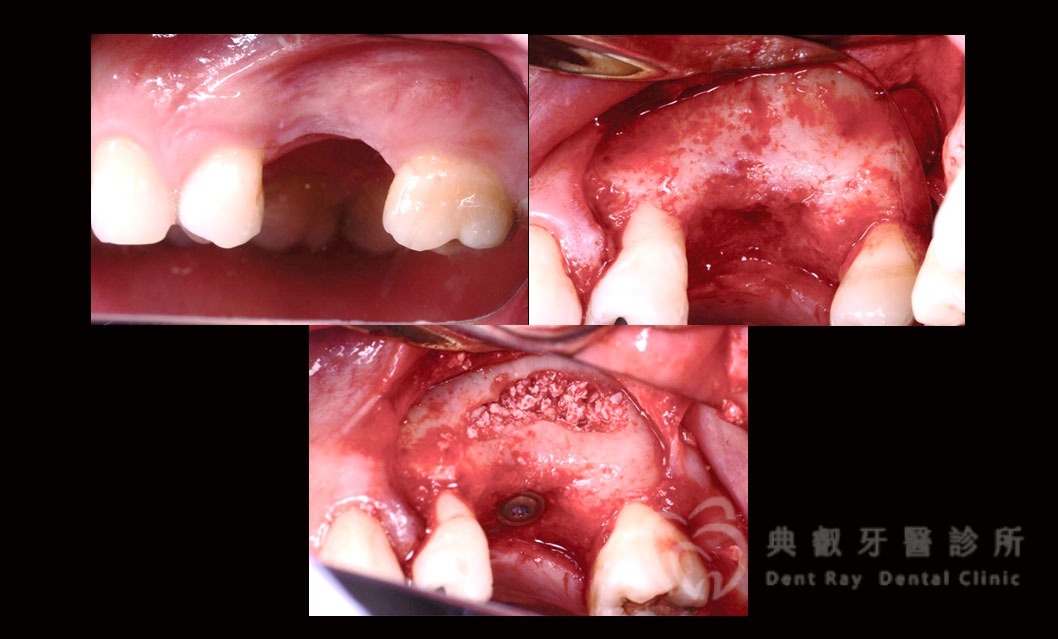

鼻竇增高術

鼻竇增高案例